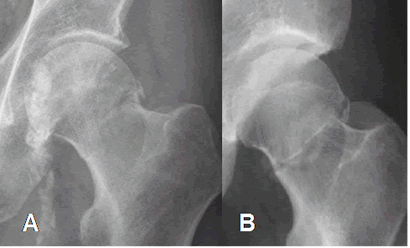

Fig 50. Fractura transcervical.

A y B: Rx AP. Fracturas transcervicales, no desplazadas.